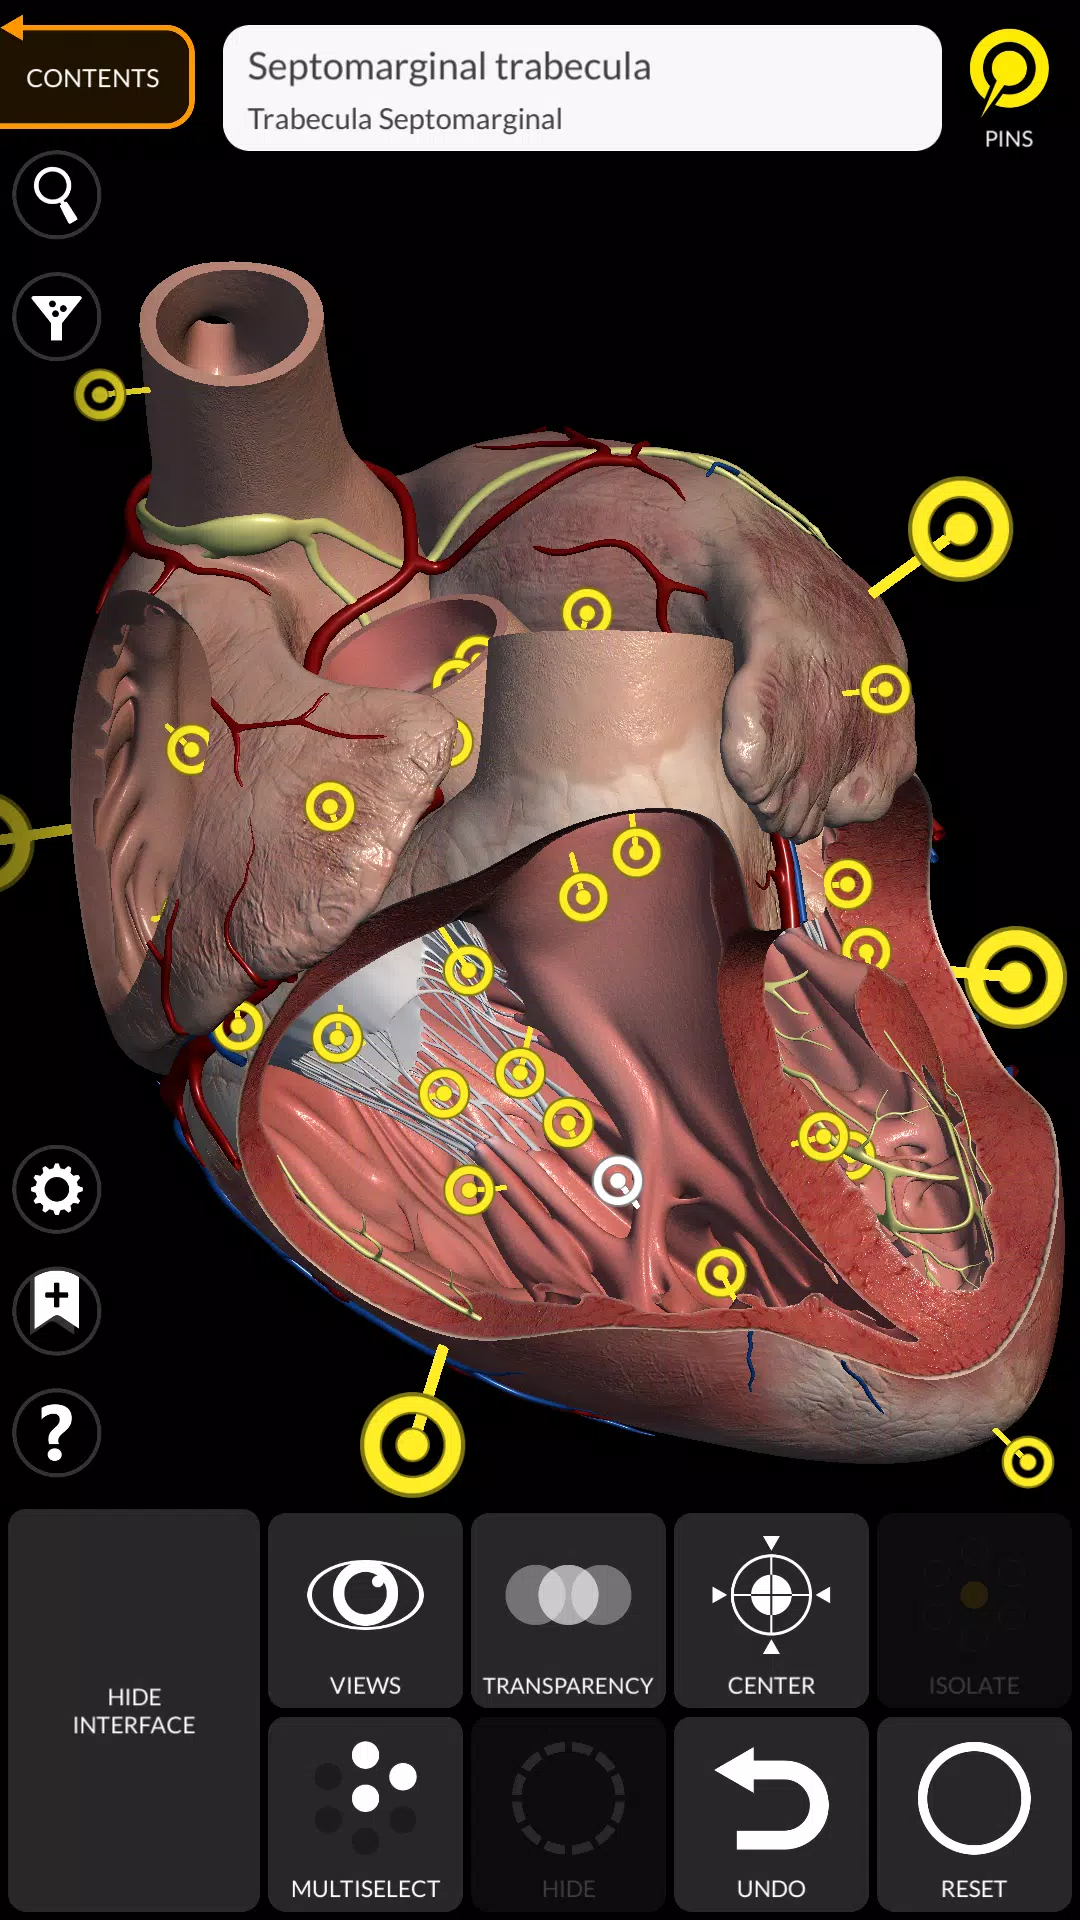

用“解剖3D地圖集”應用以引人入勝的互動方式發現人類解剖結構的複雜性。該免費下載的應用程序提供了全面的學習體驗,儘管解鎖了全部內容需要購買內置的購買。為了讓您品嚐其功能,總是可以免費訪問完整的骨骼系統和選擇其他內容,從而使您可以徹底探索該應用程序的功能。

“ Anatomy 3D Atlas”通過其用戶友好和直觀的界面徹底改變了您研究人類解剖結構的方式。您可以從任何角度檢查每個解剖結構,這要歸功於高度紋理高達4K的質地的高度詳細的3D模型。該應用程序的組織按地區和預定義的觀點簡化了對單個部分或系統組以及不同器官之間的關係的研究。

專為醫學生,醫生,物理治療師,護理人員,護士,運動培訓師以及任何渴望加深他們對人體解剖結構的理解的任何人設計,這是對傳統解剖學教科書的絕佳補充。

解剖3D模型

- 心血管系統

特徵

- 簡單直觀的界面

- 在3D空間中旋轉並縮小每個型號

- 隱藏或隔離單個或多個選擇模型的選項

- 過濾以隱藏或顯示每個系統

- 搜索功能可以輕鬆找到每個解剖部分

- 書籤功能以保存自定義視圖

- 智能旋轉自動移動旋轉中心

- 透明度函數

- 通過從淺表層到最深的肌肉的肌肉可視化肌肉

- 通過選擇模型或引腳,相關的解剖術語顯示

- 肌肉的描述:起源,插入,神經和動作

- 顯示/隱藏UI接口(小屏幕非常有用)

Anatomy 3D Atlas應用截圖